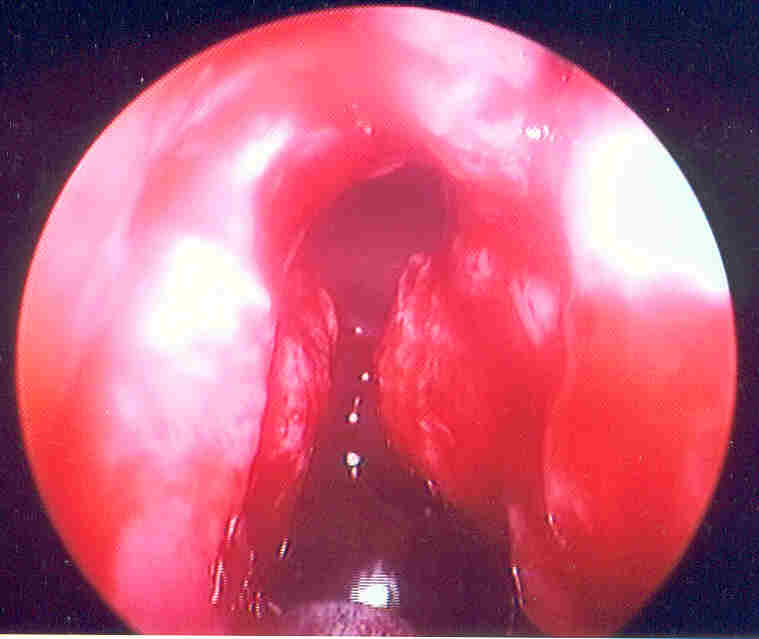

This picture depicts revision frontal sinus surgery from outside the middle meatus.  Below, the frontal outflow tract is clearly seen from below, looking up with a 70 degree scope.